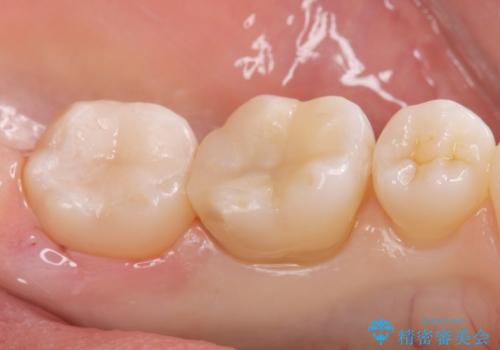

- メタルインレーが取れてしまって来院。

虫歯が再発していたので拡大鏡下で取り切った後、e-maxインレーにて治療しました。

また、一番奥の歯も古い樹脂の治療がされていたため虫歯の予防のために樹脂を取り除き、う蝕がないことを確認してe-maxインレーで治療しました。